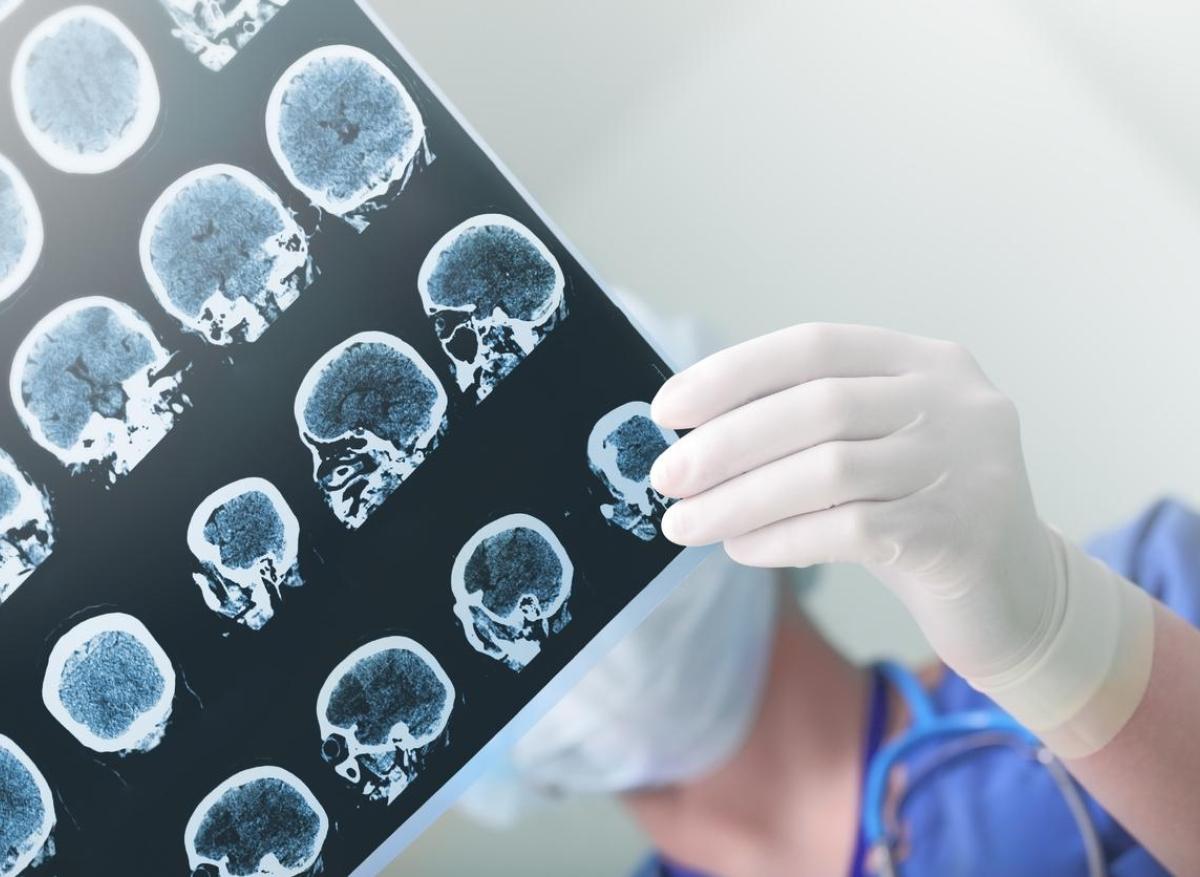

- peakSTOCK/istock